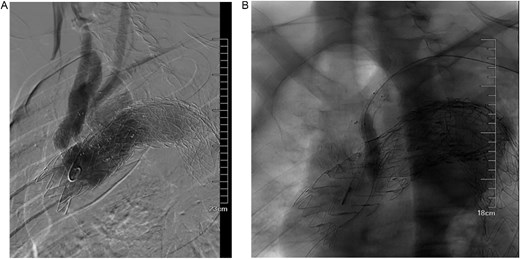

A 68-year-old male was admitted on July 14, 2023, with “intermittent blood in phlegm for over a month.” He had a history of EVAR and underwent right internal iliac aneurysm embolization (Fig. 1A) on July 18, 2019 for an abdominal aortic aneurysm (Fig. 1B). On July 1, 2022, he underwent left iliac artery stent graft implantation due to abdominal pain from a type Ib endoleak (see Fig. 1C). Computed tomography angiography (CTA) findings demonstrated that the maximum diameter of the thoracic aortic aneurysm had reached 72.64 mm and showed a 11.49 mm increase in aortic arch aneurysms over 3 years, which had been reached the established criteria for surgical intervention according to the 2022 ACC/AHA Guideline for the Diagnosis and Management of Aortic Disease [1] (Fig. 1D and E).

(A) Internal iliac artery embolization and stent graft implantation were performed. (B) Preoperative aortic CTA in 2019. (C) Type Ib endoleak from left iliac artery stent graft. (D) CTA shows the diameter of aortic arch aneurysm was 61.15 mm in July 2019. (E) CTA shows the diameter of aortic arch aneurysm was 72.64 mm in July 2022.